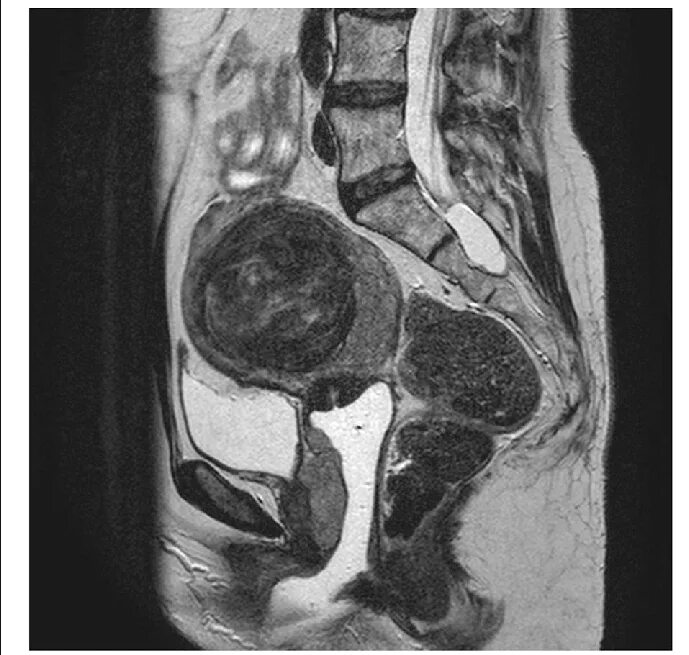

Метастазы в матке